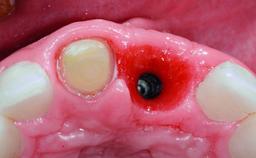

A 32-year-old female Caucasian patient with a compromised maxillary right central incisor was referred to us by a general dentist. Her chief complaints were discomfort and mobility of tooth 11 with unsatisfactory esthetics due to discoloration. The patient reported a previous trauma, some years earlier, as the origin of pathology on the afflicted tooth. Anamnesis was negative for any other dental or periodontal pathology in the remaining dentition. The patient did not take any medication and reported to be a light smoker (5–10 cigs/day). She had high esthetic expectations of her treatment. The extraoral examination revealed a high smile line with full exposure of her maxillary teeth and surrounding soft tissue in the area between the second premolars.

Bone Augmentation Horizontal|Simultaneous|Staged

Augmentation Materials Autogenous chips|Xenogenous|Membrane

Placement Protocol Early or late implant placement

Bone Volume Deficient horizontally, requiring prior grafting